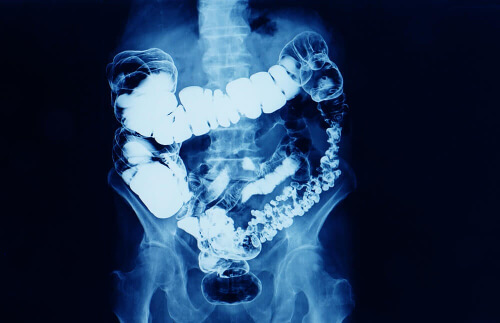

Czopki glicerynowe zawierają aktywny składnik o nazwie glicerol. Jest to substancja o działaniu przeczyszczającym podawana doodbytniczo. Efekt ten uzyskuje się, ponieważ po podaniu czopków stolec mięknie i wywołuje łagodne miejscowe działanie drażniące, pobudzając perystaltykę jelit.

- Miejscowe działanie drażniące błonę śluzową odbytu, działanie drażniące nie wpływa jednak na ściany jelit. Czopki glicerynowe powodują kurczenie się odbytnicy, sprzyjając wydalaniu kału.

- Działanie osmotyczne: glicerol ma właściwości pochłaniania wody, a to wraz z właściwościami smarującymi zmiękcza stolec i ułatwia jego wydalanie.

Działanie czopków glicerynowych objawia się od 15 minut do godziny po aplikacji. Ponadto glicerol nie wchłania się całkowicie i jelita prawie całkowicie usuwają go wraz z kałem.